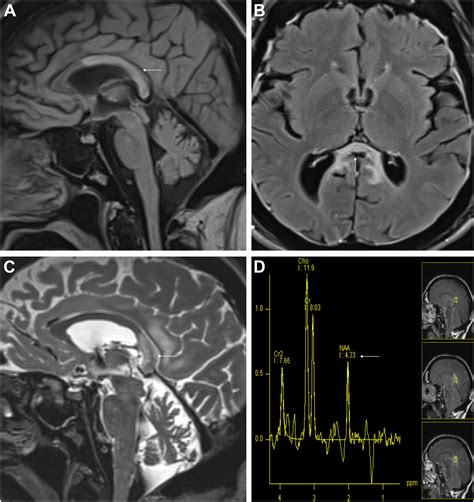

Diagnosing White Matter Disease typically relies on advanced imaging techniques rather than just clinical observation. Physicians look for specific patterns of damage that distinguish this condition from others like Alzheimer’s or stroke.

MRI (Magnetic Resonance Imaging) The gold standard for identifying white matter hyperintensities (bright spots on the scan indicating damage).

CT Scan Used to detect brain damage, although generally less detailed than MRI in identifying white matter changes.